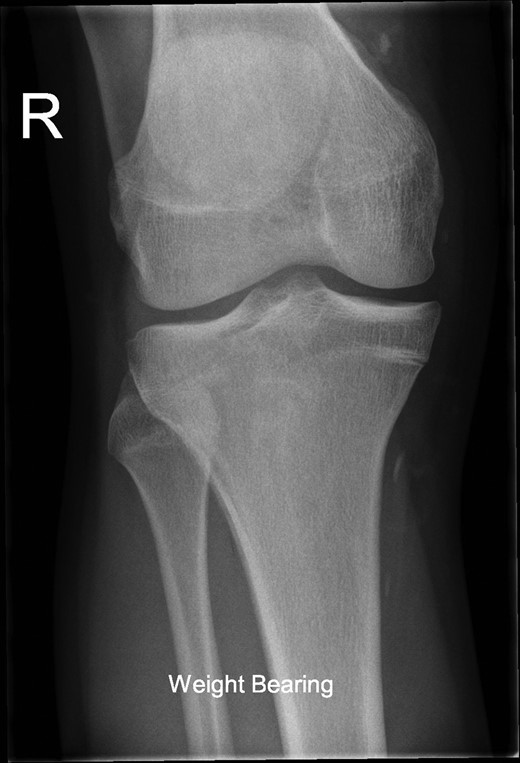

The patient's initial management was non-operative with a period of knee protection with a range of movement brace and intensive rehabilitation. Approximately 3 months after the index injury he returned to competitive football but shortly after his return sustained a further valgus injury and despite further conservative treatment was unable to return to sport. He was referred to our service with ongoing instability symptoms. Upon clinical assessment we noted an asymmetric valgus alignment of the knee and abnormal laxity of the MCL. Radiographic investigations revealed an abnormality of the lateral distal femur and alignment radiographs confirmed the valgus mal-alignment with abnormal opening of the medial tibio-femoral joint space on single-leg stance radiographs (Figs 2–4). We obtained the patient's MRI scan and reviewing this with Radiology colleagues revealed subtle changes of increased lateral femoral physis fluid density on T-2 weighted images consistent with a Salter Harris Type V injury (Fig. 5).

Radiograph demonstrating opening of the medial compartment and increased valgus alignment on single-limb weight bearing.